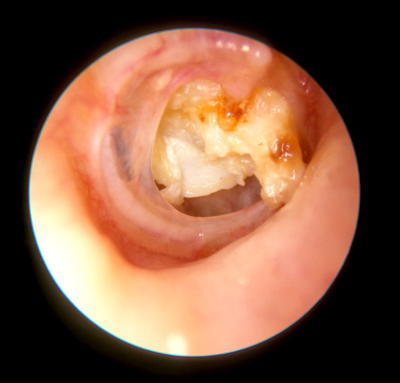

Question 4

Question

Describe image

Answer

Air bubbles seen

Acute otitis Externa

Petrositis

Mastoiditis